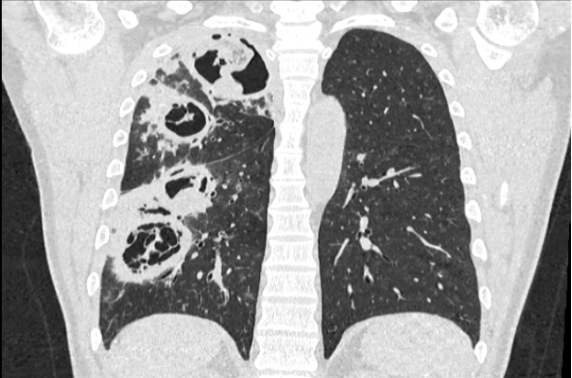

• 2025年1月26日内胸部CT示:右肺多发空洞,周围伴“树丫征”。

视频1:患者入院后胸部CT(2025-01-26)

• 2月5日(拔管后)复查胸部CT:左肺上叶空洞病变较前次增大,右肺病变较前改善(视频2)

视频2:患者入院后第2天胸部CT(2025-02-05)

图片

1 患者胸部CT冠状面—右肺空洞样病变